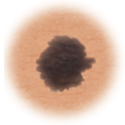

Moles (nevi)

Small skin marks caused by pigment-producing cells in the skin. Moles can be flat or raised, smooth or rough, and some contain hair. Most moles are dark brown or black, but some are skin-colored or yellowish. Moles can change over time and often respond to hormonal changes.

Most moles are benign and no treatment is needed. Some benign moles may develop into skin cancer (melanoma). See below for signs.

Distinguishing benign moles from melanoma

Certain moles are at higher risk of changing into malignant melanoma, a form of skin cancer. Large moles that are present at birth and atypical moles have a greater chance of becoming cancerous. Finding cancerous skin growths early is important because that’s when treatment is most likely to be effective. Removing the melanoma through surgery seems to work best as the treatment. When a melanoma is diagnosed early, surgery usually removes all the cancer.